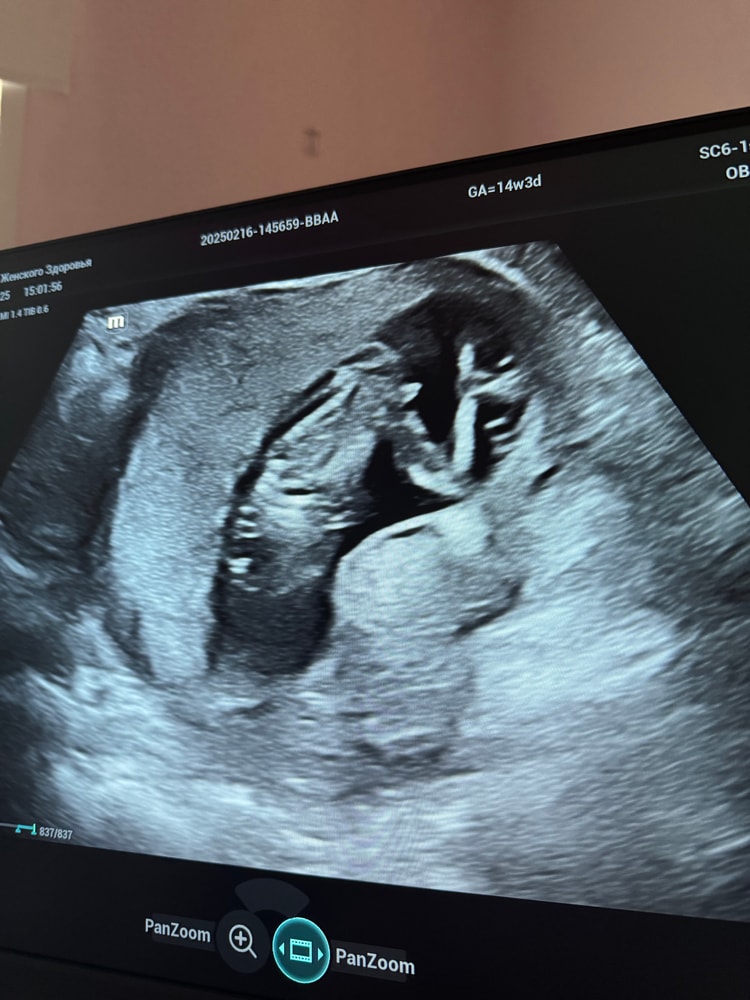

Малышка или малыш 👶

Пол малышаходили на 16й неделе на узи сказали пацан , пришли потом на узи через 2 недели (у мужа день рождения был хотели точно узнать и гендер пати сделать) сказали уже девочка Первое фото 16 недель , второе 18 и вид снизу на пуповине сидит